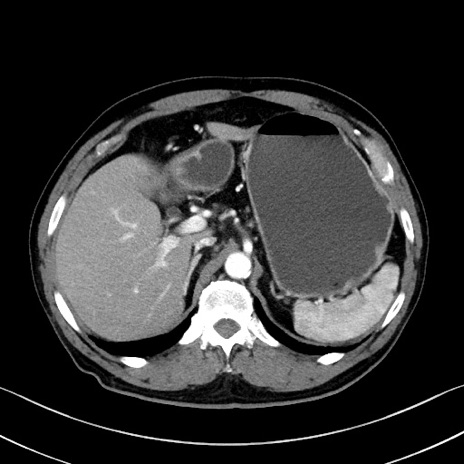

症例35(横断像)

冠状断像

【症例】70歳代 男性

【主訴】腹部膨満、嘔吐

【現病歴】昨日より腹部膨満感出現。本日増悪し、仙痛出現。嘔吐あり、受診。

【既往歴】糖尿病、胆摘後

【身体所見】BP 149/80mmHg、HR 74/min、BT 35.9℃、腹部:膨満、軟、圧痛なし。腸雑音減弱あり。上腹部正中切開瘢痕あり。

【データ】WBC 13500、CRP 1.72